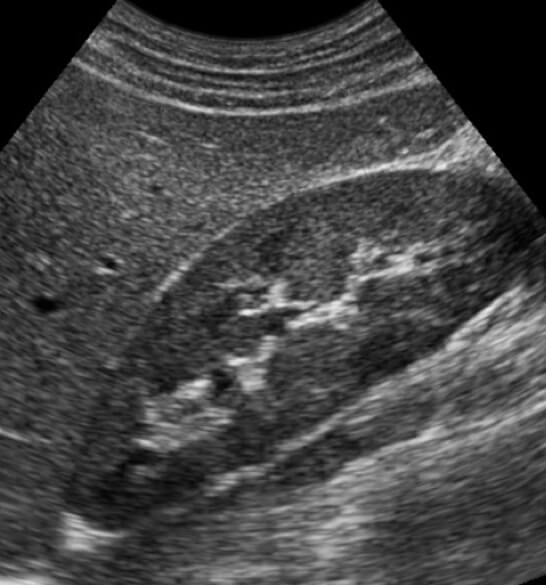

Renal Biopsies

When patients present with kidney failure, they often need to undergo a kidney biopsy to help determine the cause for this change. IR performs these procedures using imaging (CT or ultrasound) to guide a needle directly into the kidney. Tissue can then be obtained which can be evaluated by pathology to help arrive at a diagnosis.